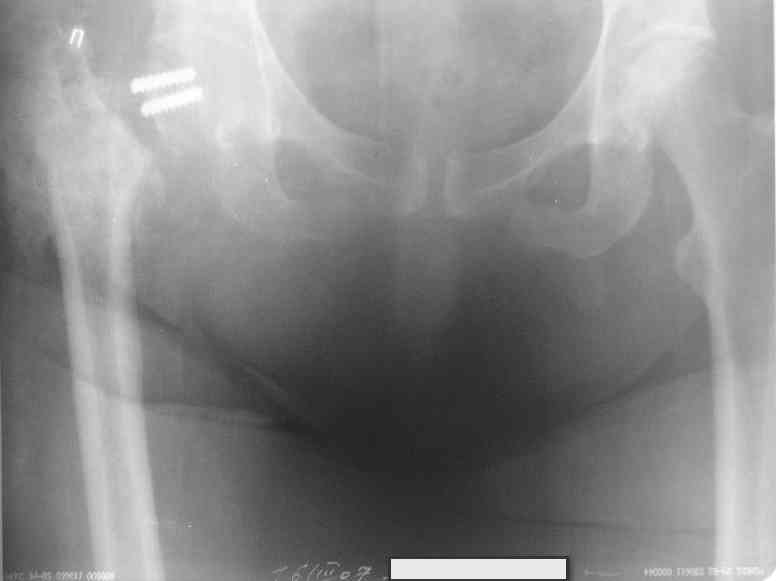

Уважаемые коллеги, хотелось бы услышать ваше мнение по следующему случаю: Относительно молодая женщина(39 лет), поступила в клинику в марте 2005 года, через 3 месяца после травмы с Неправильно срастающимся поперечным межвертельным переломом правого бедра. Был выполнен закрытый интрамедуллярный остеосинтез правого бедра канальным реконструкционным стержнем ChM. Ожидали бОльших проблем на операции, результату обрадовались. Как оказалось, зря. Сращение наступило через 3,5 месяца после операции. В ноябре 2005 года произошел перелом шейки бедра и винтов в ней. В апреле 2006 импланты были удалены. В приложении фото и рентгенограммы больной. Сопутствует ожирение 4 ст. (при росте 168 см., вес больной 140кг.), сахарный диабет II тип. Имеется медиальная неустойчивость коленного и голеностопного суставов, при нагрузке колено вальгируется на 15-20 градусов. Вопросы: 1.Целесообразность эндопротезирования (в настоящий момент передвигается на ходунках)? 2.Если ответ на первый вопрос-да, то каким протезом? 3. С какими проблемами можем столкнуться во время и после операции? Заранее благодарен за ответы. Салават Салаватов, Екатеринбург